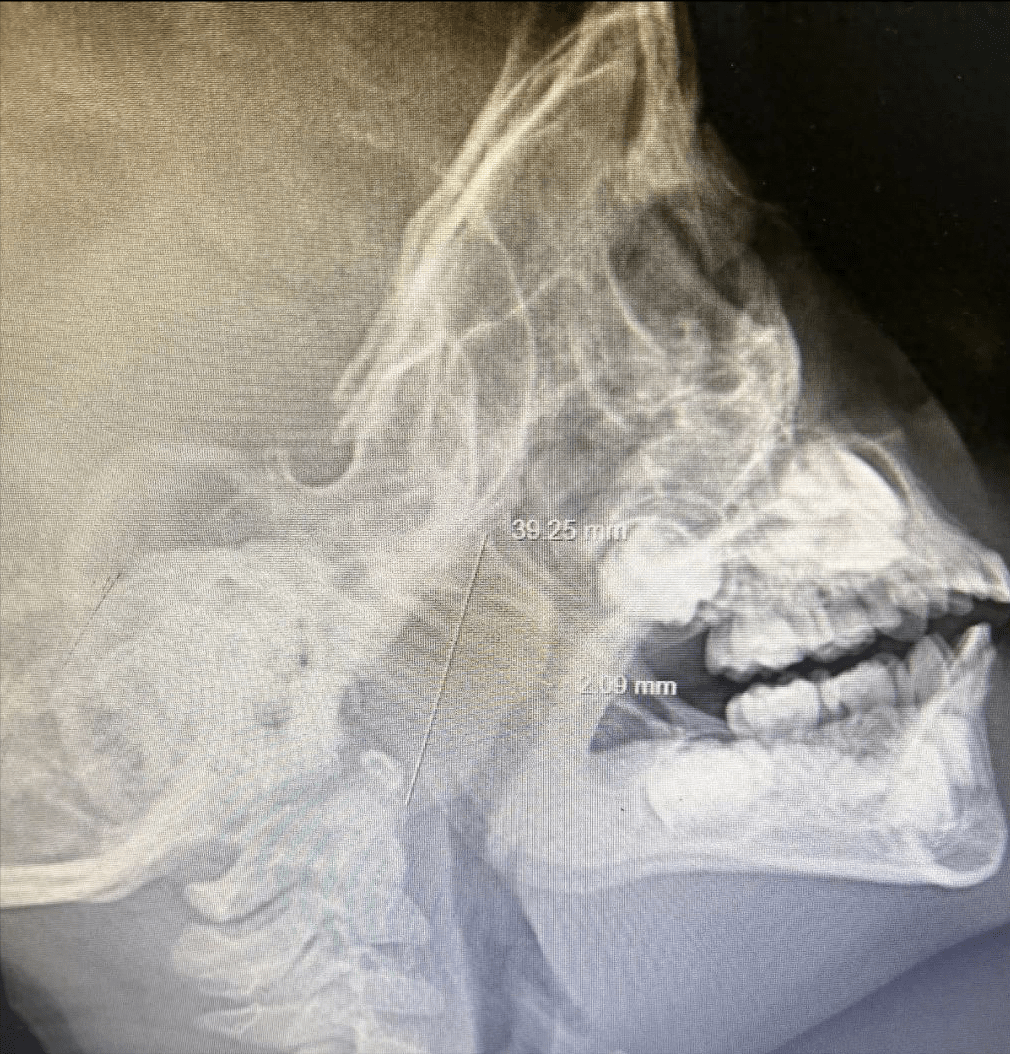

临床急诊影像诊断之---鼻骨骨折ppt